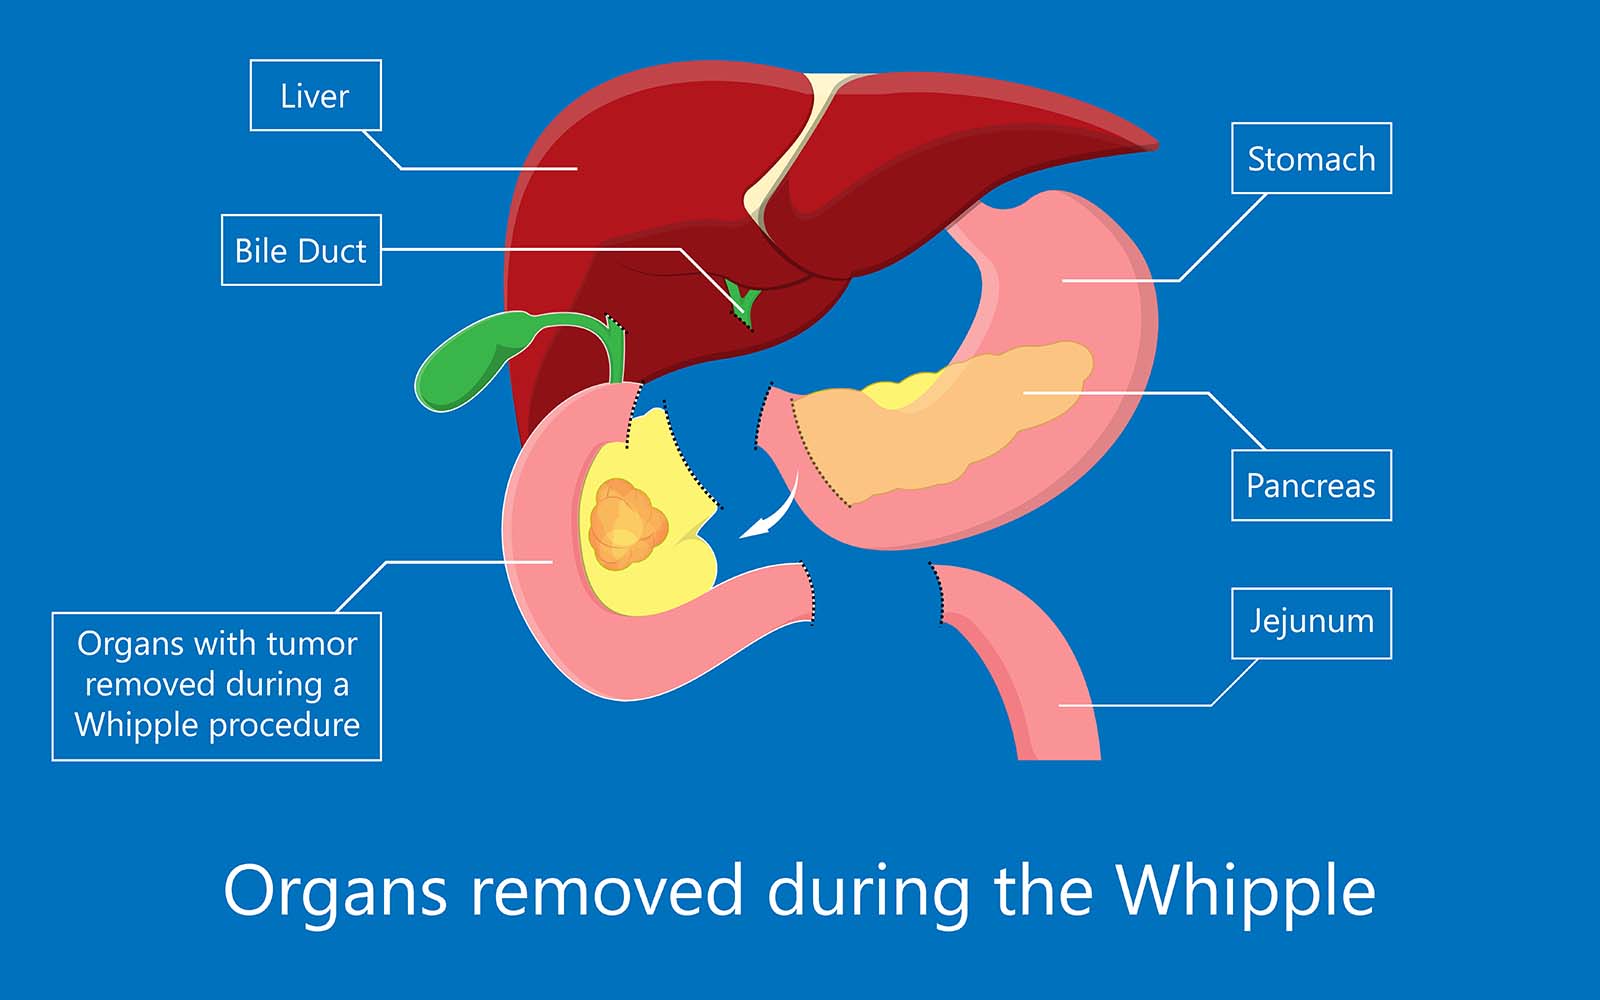

Pancreatectomy Pancreatic Resection Surgery Pancreatic Cancer Resection

Whipple Procedure Diagram

https://scmsc.com/wp-content/uploads/2023/03/Organs-removed-during-the-Whipple.jpg

Whipple Procedure Steps